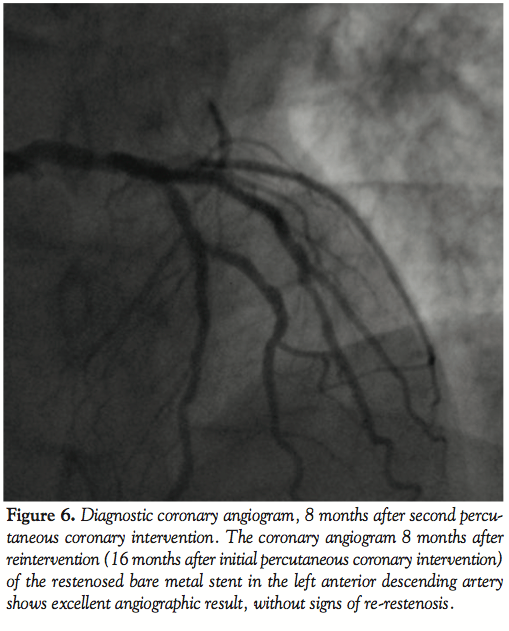

Follow-up. Eight months after the second procedure, the patient was referred again to our center. The patient had complaints of atypical chest pain, which was different than his previous presenting complaints. A diagnostic coronary angiogram was performed and showed very good result of the treaded ISR and bifurcation lesion of the LAD-D1; no new ISR was seen (Figure 6). The stent in the PL branch was also patent. Fractional flow reserve on the previously known 40% lesion of the ostium of the RCx was 0.95. In conclusion, there were no lesions found that could explain the atypical chest pain of the patient and the patient was referred back to his general cardiologist for further exploration of his complaints.